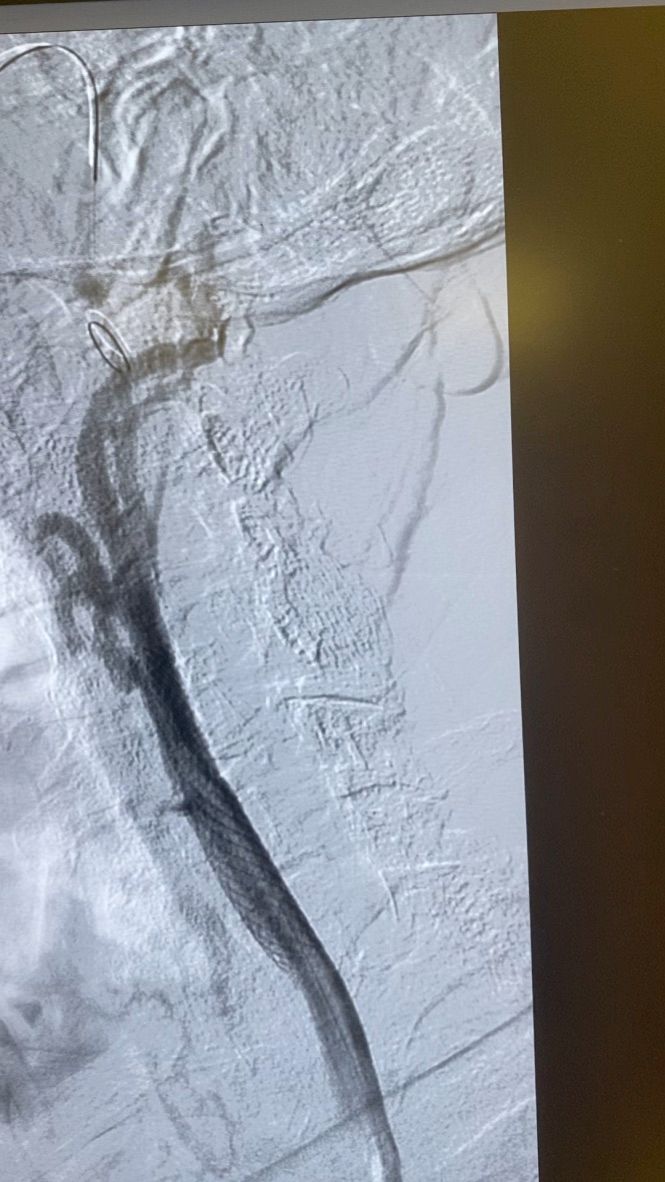

Dal 1997 al 2009 ha lavorato a tempo pieno presso Maria Cecilia Hospital di Cotignola come Cardiologo interventista eseguendo procedure interventistiche di PTCA sul distretto coronarico, carotideo, PTA del distretto iliaco-femorale, renale, e tibiale; Procedure percutanee di impianto di endoprotesi nel in aorta toracica e addominale, impianto percutaneo di valvole aortiche (TAVI), chiusura di Difetti interatriali e forami ovali.

VALUTAZIONE DI PROCEDURE INTERVENTISTICHE (vascolare, patologie delle carotidi, delle arterie iliacofemorali, arterie tibiali nel piede diabetico, aorta addominale e toracica) E CARDIOLOGICHE (angioplastiche coronariche, TAVI, chiusura di difetti interatriali e forami ovali pervi)